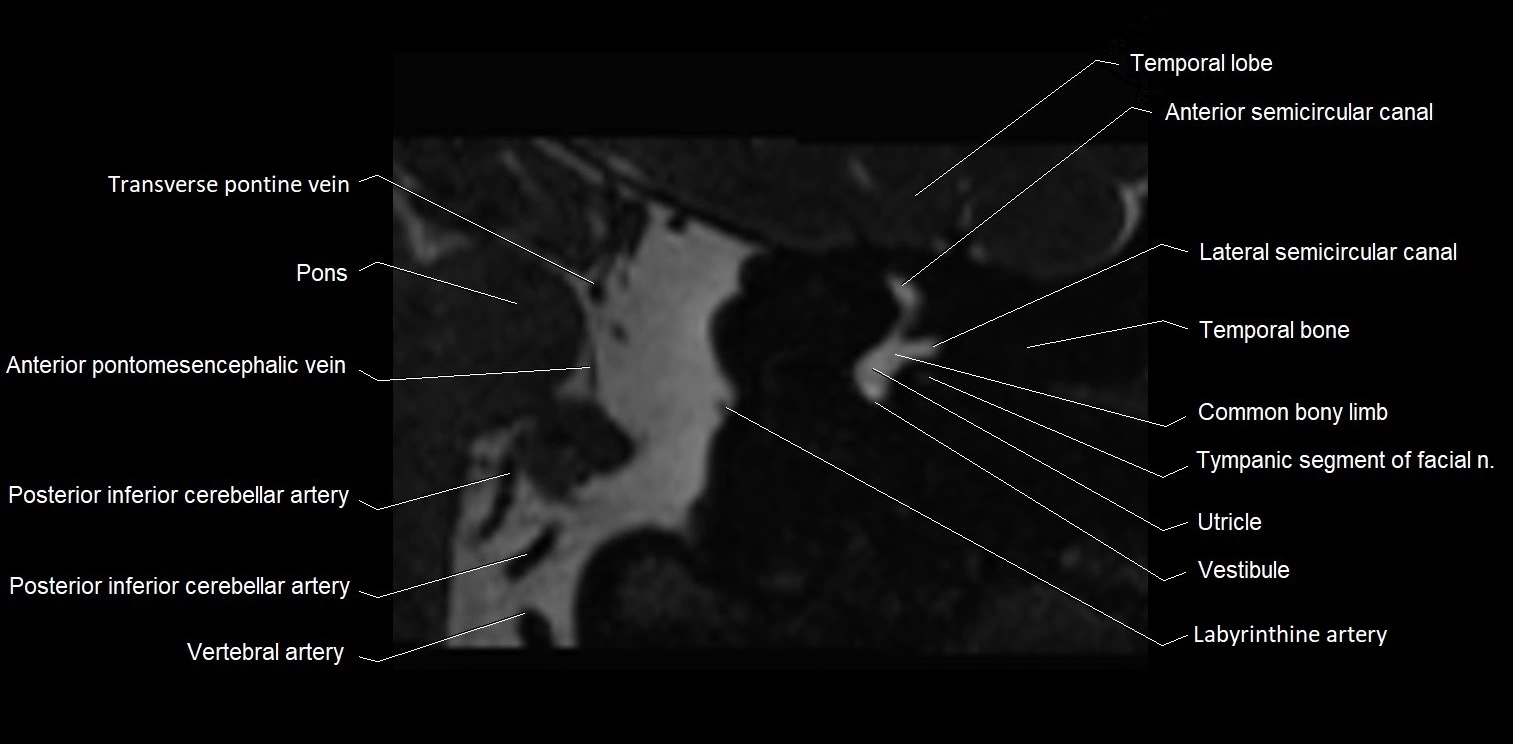

MRI images

image